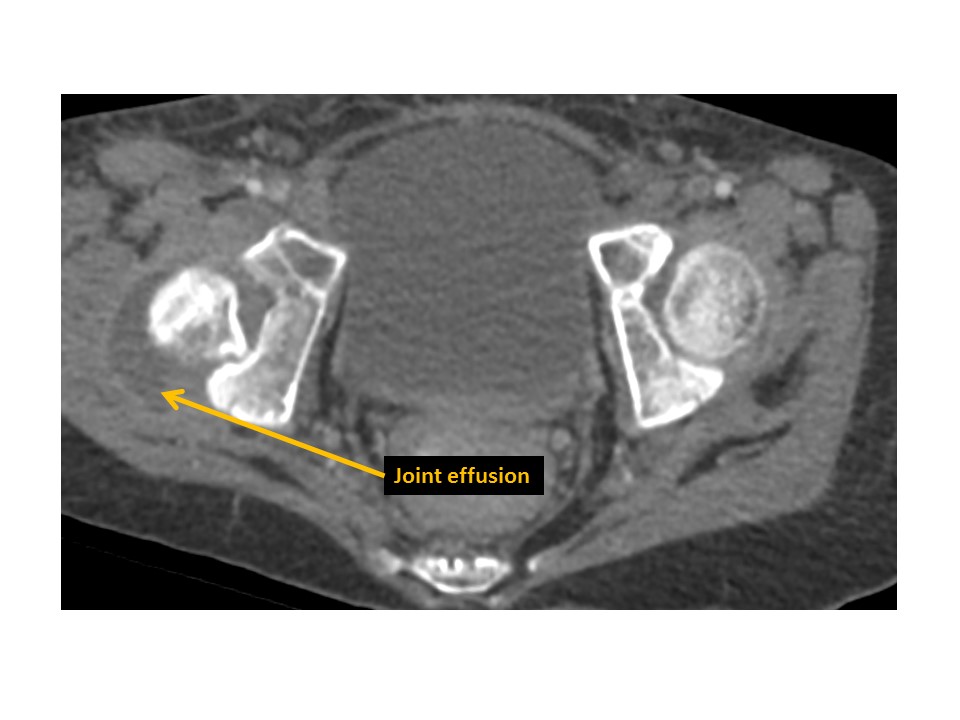

HIPS/PROXIMAL FEMURS

There is hip osteoarthritis or inflammation. [Yes/No]

There are hip joint effusions. [Yes/No]

There are intra-articular bodies within the hip joints. [Yes/No]